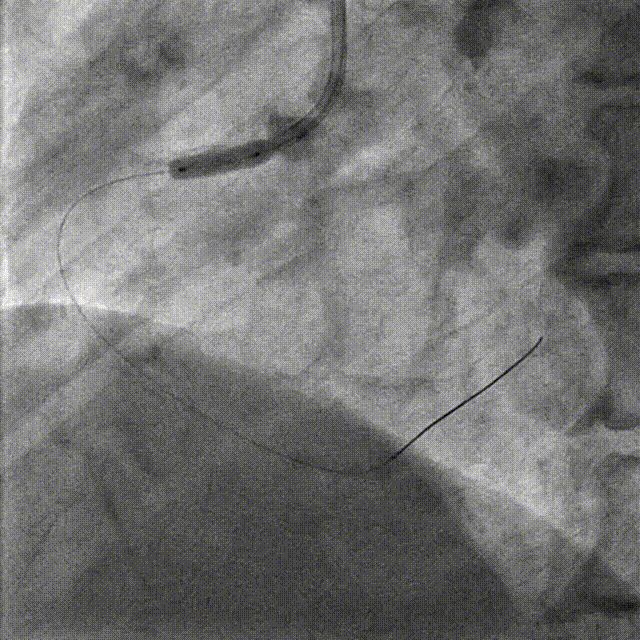

PCI-LAD TR, 7F EBU3.5

ROTA with 2.0mm burr

Angiography & Angioplasty NC 2.5*12mm